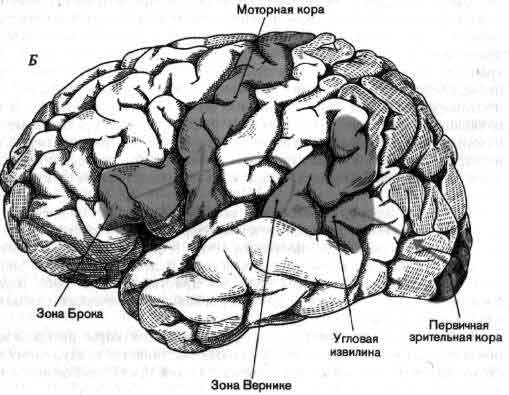

Схема чувствительных зон новой коры мозга